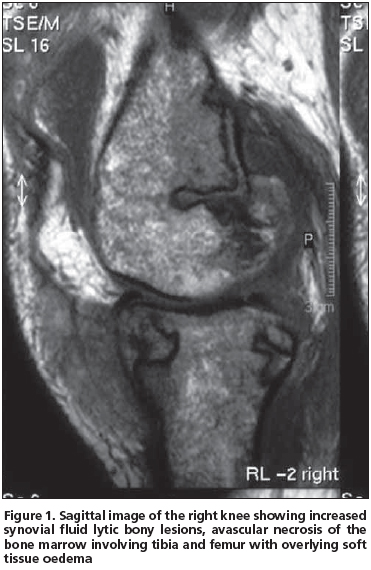

Magnetic resonance imaging of the left knee showed increased amount of joint fluid, synovial contrast enhancement, destructive changes of cortical bone in non-weight-bearing regions of the femur and tibia, and multiple foci of abnormal signal intensity. These findings were compatible with the diagnosis of fat necrosis secondary to acute pancreatitis (Figure 1). Synovial biopsy was performed endoscopically, which revealed coagulation necrosis areas, a few multinuclear cells and areas of fibrous tissue and fatty tissue.

Arthralgia (or arthritis) is listed among the presenting symptoms of this triad in one- fourth of the cases[1,3,6-8] as was also observed in our patient. Between 50% and 88% of the patients have joint manifestations at some time during the syndrome[4,9]. Although metacarpophalangeals, knees and ankles are the most commonly affected sites[4,9], any joint can be involved, mimicking rheumatoid arthritis, gout and septic arthritis. Our patient's arthritis occurred in both knees. Although systemic manifestations of this syndrome may include polyserositis, mental status changes, medullary fat necrosis of long bones and aseptic necrosis of the bones were less frequently observed[1,4,7]. As mentioned, medullary fat necrosis of both femurs developed in our patient. The radiological appearance of medullary fat necrosis is characteristic, with osteolytic lesions and motheaten bone destruction and periostitis of the tubular bones of the extremities, which correlate pathologically with areas of extensive intramedullary fat necrosis and trabecular bone destruction.